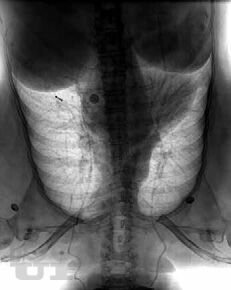

Лучевая диагностика заболеваний молочной железы

В одной книге представлен обзор случаев типичных проявлений заболеваний молочной железы, выявляемых при маммографии, ультразвуковом исследовании и магнитно-

резонансной томографии. Дано краткое описание того, как выполнить биопсию и другие процедуры на молочной железе с использованием каждой из трех методик. Простой формат,

четкая структура материала и ссылки на источник в конце описания каждого случая помогут начинающему врачу принимать правильные решения.